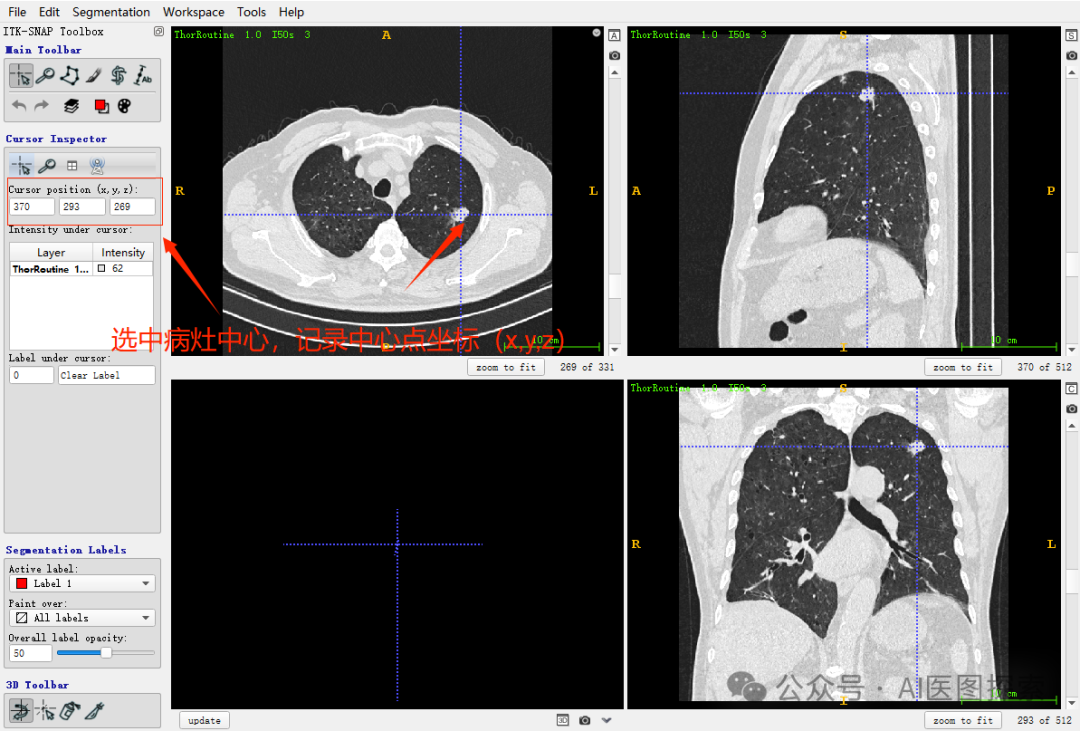

坐标记录样例,以ITK-SNAP软件为例: